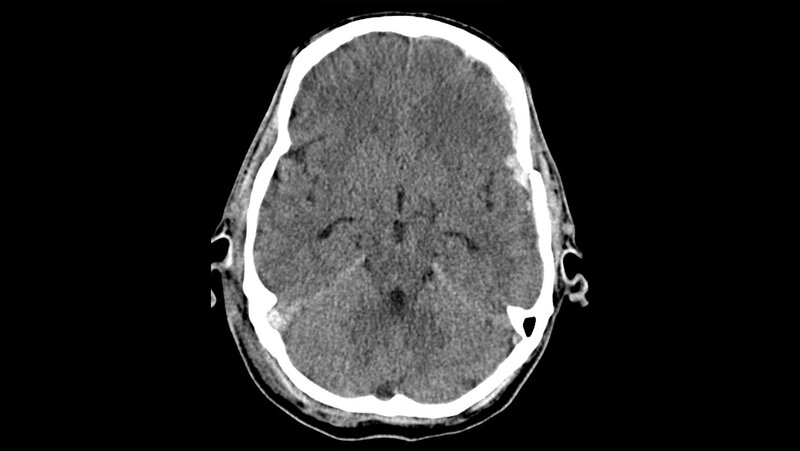

Der Kopf wird mit am häufigsten im CT und MRT untersucht. Neben alltäglichen Indikationen sind vor allem die Schädel-Hirn-Traumata ein Grund, weshalb die Bildgebung unverzichtbar ist. Unauffällig wirkende Patienten können im Verlauf schwerwiegende Folgen davontragen. In diesem Artikel gehen wir auf das allgemeine Schädel-Hirn-Trauma und dessen Diagnostik im CT und MRT ein. Es werden Besonderheiten und viele Tipps und Tricks genannt, die den Alltag einfacher gestalten sollen.

Schlüsselwörter: Schädel-Hirn-Trauma, SHT, Hämatom, Blutung, MRT, CCT